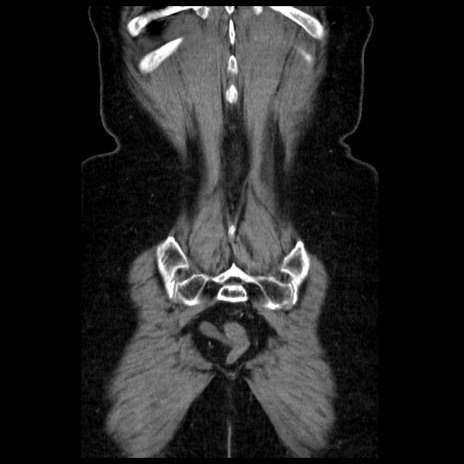

症例13(冠状断像)

【症例】70歳代女性

【主訴】腹痛、嘔吐

【現病歴】15時間程前(昨晩)より腹痛あり。今朝になっても症状の改善なく、嘔吐あり。腹痛も増悪あり、救急外来受診。

【既往歴】子宮癌全摘術後

【身体所見】意識清明、BP 121/72mmHg、P 74bpm、SpO2 100%(RA)、腹部:平坦・軟、腸雑音ほぼ聴取せず。下腹部・心窩部・臍左上に圧痛あり。反跳痛なし。

【データ】WBC 10600、CRP 0.15